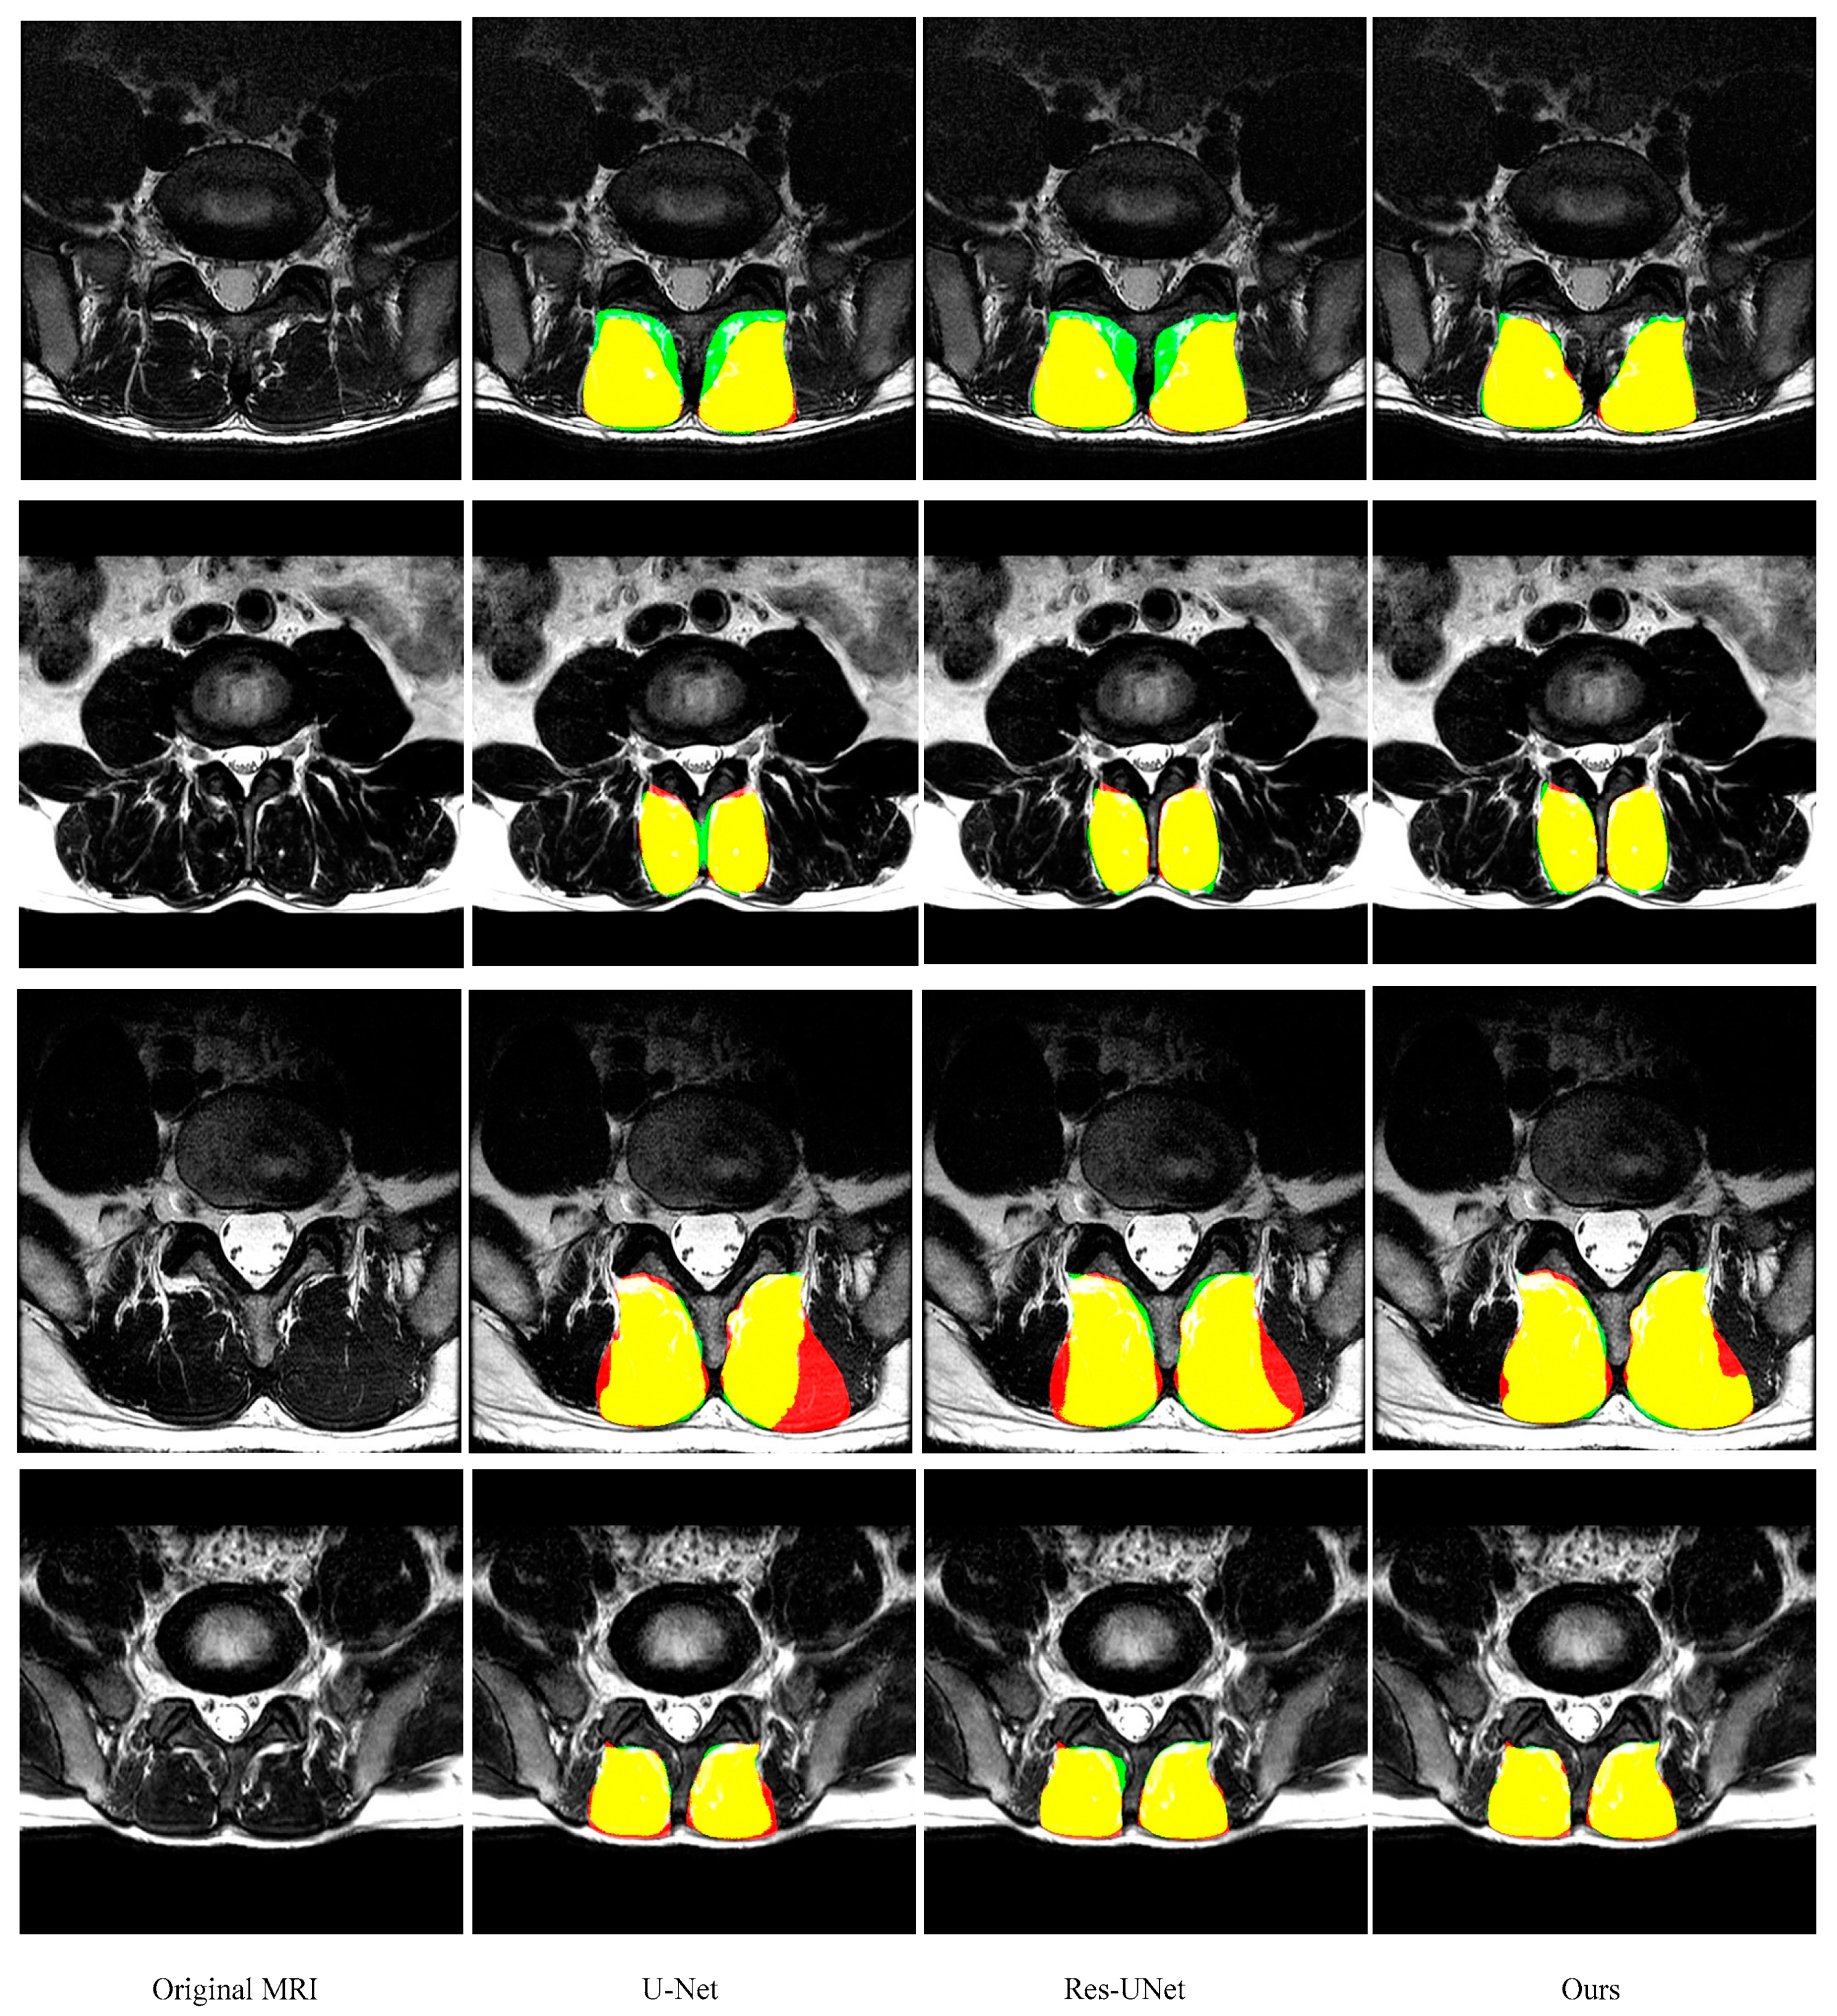

3.5. Comparison with other State-of-the-Art Methods

| U-Net | 0.921 ± 0.039 | 0.925 ± 0.049 | 0.920 ± 0.056 | 6.16 ± 5.14 |

| ResU-Net | 0.944 ± 0.043 | 0.946 ± 0.063 | 0.945 ± 0.045 | 4.68 ± 3.25 |

| Ours | 0.949 ± 0.034 | 0.951 ± 0.046 | 0.950 ± 0.035 | 4.62 ± 2.81 |